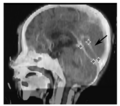

We are introducing a new approach for landmark-based deformable image registration. Our method uses Gaussian radial basis functions (RBFs) to define a vector field from point landmarks, and applies regularization based on the vector field second order derivative.

Our approach is based on the fact that the Gaussian RBF has infinite support, but the influence of each RBF is localized, making this method well suited for local corrections. In addition, Gaussian RBFs have a distinct advantage over competing approaches such as Wendland functions, because the regularized vector field can be solved exactly with a simple equation. Our plan for the project week is to implement our registration algorithm as a Slicer plugin.

Algorithm for the landmark-based registration has has been implemented as a part of out in-house software Plastimatch. The method has been validated on a large landmark sets available for download on DIR-LAB web site. This work has been submitted for publication to IEEE Transactions on Medical Imaging.